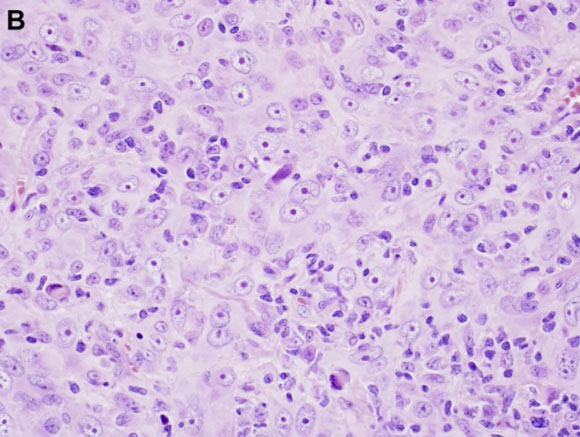

Lymphoblastic lymphoma, the cytology not predictive of phenoty[e (left is B-cell, right is T-cell, or maybe vice versa? you would never know)

Micro: medium sized c scant cytoplasm, inconspicuous nucleoli

- PB has cells c delicate chromatin convoluted nuclear membranes, freq mits, sometimes cytoplasmic vacuoles

- Lymphoma (T-LBL) can look like starry sky, c lots of pericapsular and soft tissue infiltrates